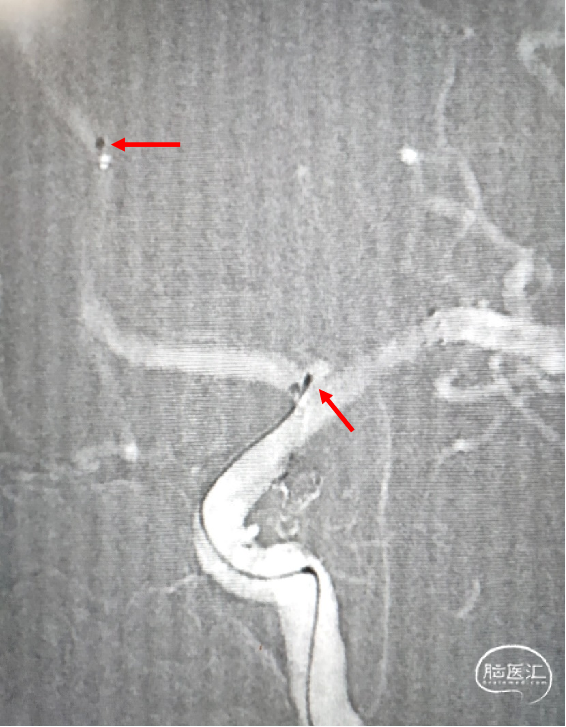

颅脑DSA

临床诊断:左侧颈内动脉分叉部宽颈动脉瘤;左侧颈内动脉后交通动脉瘤支架辅助栓塞术后。

动脉瘤尺寸:2.7*2.1mm

患者动脉瘤位于颈内动脉分叉部,部分瘤颈累及A1;动脉瘤破裂出血的风险相对较高,需要手术干预。该动脉瘤属宽颈,单纯弹簧圈栓塞,弹簧圈易脱出,需支架辅助栓塞。病人选择支架下弹簧圈栓塞治疗技术。

患者一期使用Solitaire支架治疗同侧颈内交通段动脉瘤,且支架远端落点位于M1段。根据前期治疗情况,有两种支架释放方案:

A:支架整段释放于左侧大脑前A1段,与一期释放的支架呈“T”型,难点在于支架近端落点的精准把握。

B:支架头端释放于A1段,尾端落于颈内段,与一期释放的支架呈“Y”型。缺点是支架在交叉及重叠区域打开不良导致血栓事件发生的可能性大。

为充分保护分支血管使手术顺利进行,拟选择A方案,使置于A1段的支架与一期释放的支架呈“T”型,如此既能很好地保护瘤颈,也能避免做“Y型”时支架交叉及重叠区域打开不良;选择具有较高金属覆盖率且没有无效工作端的LEO+Baby编织型支架,能为术者提供更多的操作空间,更好完成支架近端定位;同时其高的金属覆盖率可降低复发可能。